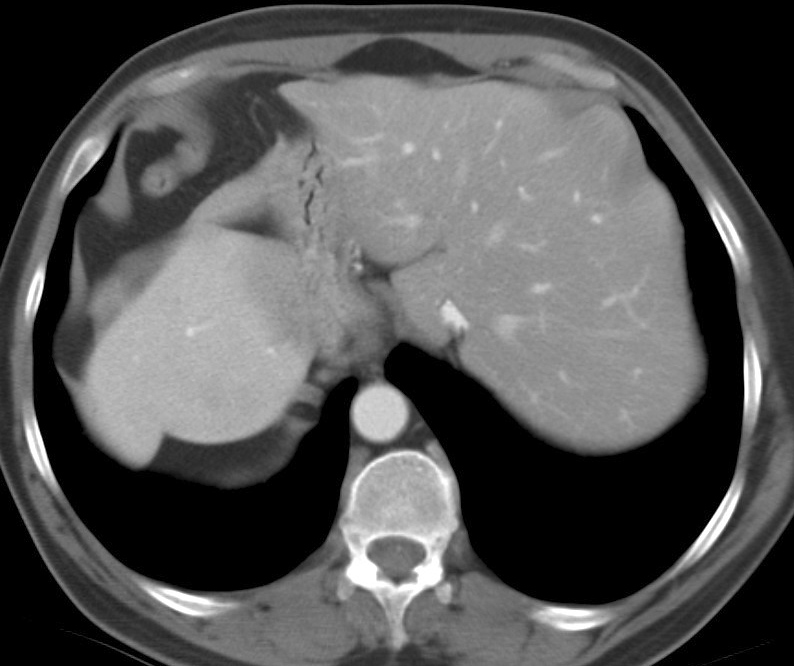

For Morgagni Ex 1 CT (b)

For Morgagni

Ex 1 CT (b)